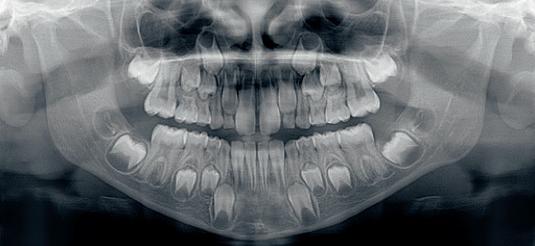

RTG DZIECI

Zdjęcie pantomograficzne - program pediatryczny

Pantomogram jest nieodzownym badaniem wstępnym podczas leczenia ortodontycznego.

Zaletami badania przy pomocy pantomografu jest uzyskanie zdjęcia o dużym zakresie obrazowania przy relatywnie niskiej dawce promieniowania.W związku z tym program pediatryczny polega na skróceniu czasu wykonywanej ekspozycji oraz zmniejszeniu pola naświetlania, co decyduje o znacznym obniżeniu dawki promieniowania.

Mając na uwadze dobro dzieci nasze aparaty dysponują specjalnym oprogramowaniem umożliwiającym znaczną redukcję promieniowania przy zachowaniu wysokiej jakości zdjęć.